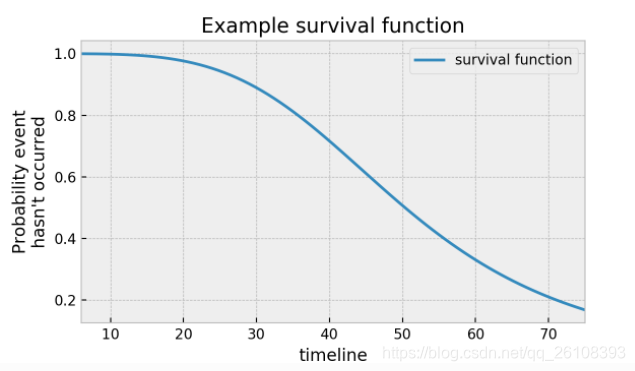

我们设 是一个随机变量,它表示一个样本的从出生到死亡所经历的时间。T总是大于0的,有可能是无穷。对一个群体,我们定义生存函数

是一个随机变量,它表示一个样本的从出生到死亡所经历的时间。T总是大于0的,有可能是无穷。对一个群体,我们定义生存函数 如下:

解释: 描述了这个群体的样本生存时间大于

描述了这个群体的样本生存时间大于 的概率,换句话说,直到时刻

的概率,换句话说,直到时刻 ,我们仍然没有观测到death事件的发生。

,我们仍然没有观测到death事件的发生。

它有以下几个性质:

。

。 ,

,  是随机变量

是随机变量 的累积分布函数。

的累积分布函数。 是一个单调不增的函数。

是一个单调不增的函数。

的函数图像可能是下面这个样子:

的函数图像可能是下面这个样子: